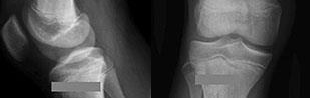

A 15-year-old male presents with deep knee pain awakening him at night. Radiographs show a permeative destructive lesion in the distal femoral metaphysis with a 'sunburst' periosteal reaction and Codman's triangle.

Biopsy confirms high-grade conventional osteosarcoma. What is the most critical prognostic factor for long-term overall survival in this patient?

Explanation

For localized high-grade osteosarcoma, the most important prognostic indicator is the histologic response to neoadjuvant chemotherapy. This is evaluated during the definitive resection. A 'good response' is typically defined as greater than 90% or 99% tumor necrosis. Patients who achieve this level of necrosis have a significantly improved disease-free and overall survival rate compared to 'poor responders' who have extensive viable tumor cells remaining.